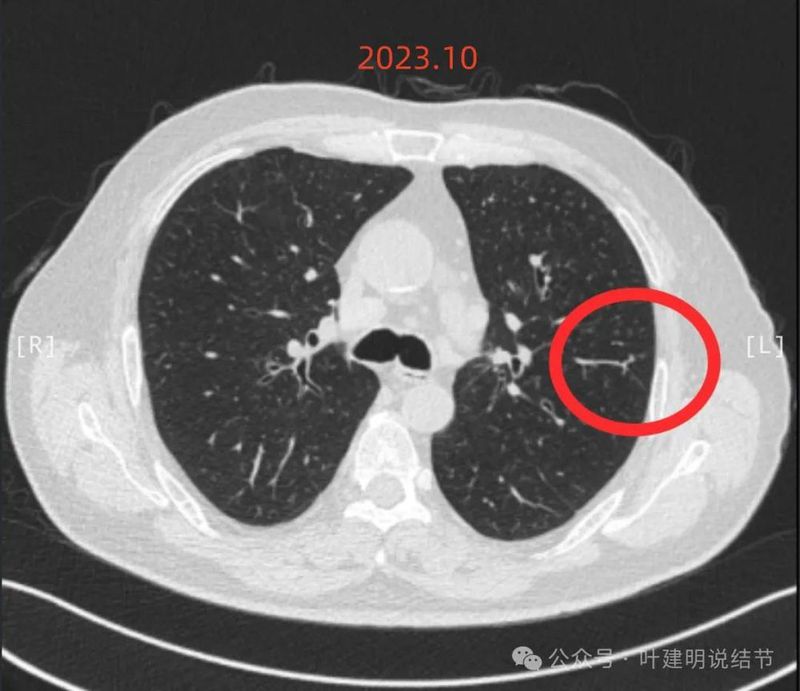

回顾看2023年10月时左上叶此处略有异常,微小实性结节,有血管与之相连。

右上叶另有实性结节,密度较高,边缘略显糊。